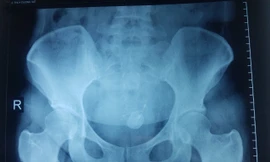

TPO - Đặt vòng tránh thai hơn 8 năm, thời gian gần đây, chiếc vòng tránh thai của bệnh nhân nữ bắt đầu đẩy xuyên cổ tử cung chui vào trong ổ bụng và rơi vào bàng quang gây ra sỏi bàng quang.